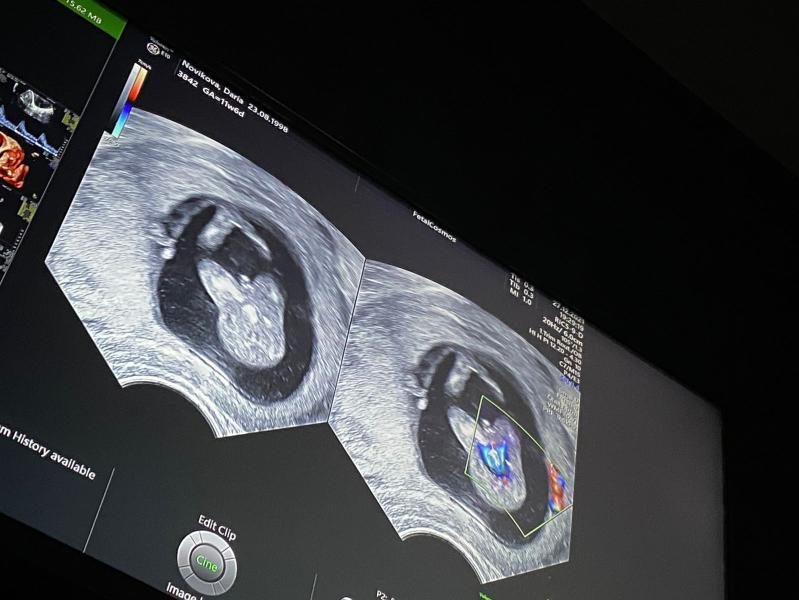

Вчера были на скрининге. Дочка показала пенис… возможно, что в итоге это дочка судя по фото, или все таки тут без вариантов уже? 😁 мы с мужем очень хотели дочку, но похоже все идёт не совсем по плану теперь))